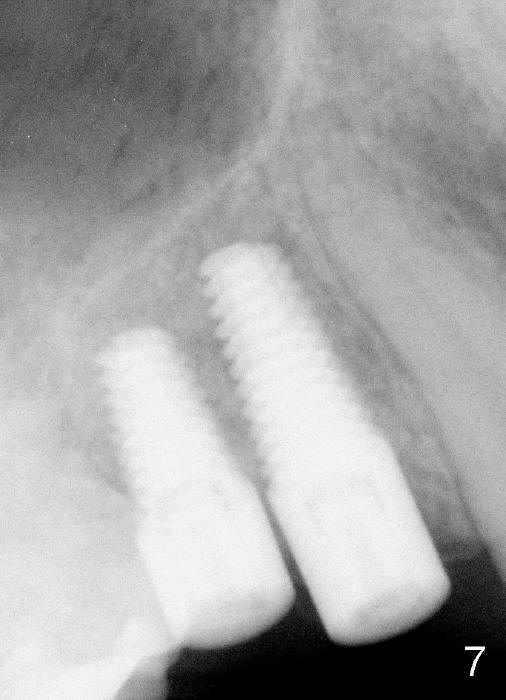

8. 4.5x17 tap, implants, torque wrench (4.5x11 and 4.5x14 mm tapered implants were placed at the sites of #4 and 5, respectively (Fig.6))

11. Fig.7: 4.5 months post implantation.  With retention of roots, the bone retains.  Implants placed can be long and easy, whereas long-term missing teeth leads to reduction in bone height